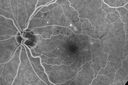

Diabetic Macular Ischemia - Enlarged FAZ - OCT-A447 views70 year old female diagnosed with diabetes 2 years ago. Her blood pressure was normal at 116/73. She has vision loss for 6 months in both eyes. VA is 20/100 OU. OCT-A shows macular ischemia.

Diabetic Macular Ischemia - Enlarged FAZ - OCT-A432 views70 year old female diagnosed with diabetes 2 years ago. Her blood pressure was normal at 116/73. She has vision loss for 6 months in both eyes. VA is 20/100 OU. OCT-A shows macular ischemia.

Diabetic Macular Ischemia - Enlarged FAZ - OCT-A426 views70 year old female diagnosed with diabetes 2 years ago. Her blood pressure was normal at 116/73. She has vision loss for 6 months in both eyes. VA is 20/100 OU. OCT-A shows macular ischemia.

Diabetic Macular Ischemia - Enlarged FAZ - OCT-A395 views70 year old female diagnosed with diabetes 2 years ago. Her blood pressure was normal at 116/73. She has vision loss for 6 months in both eyes. VA is 20/100 OU. OCT-A shows macular ischemia.